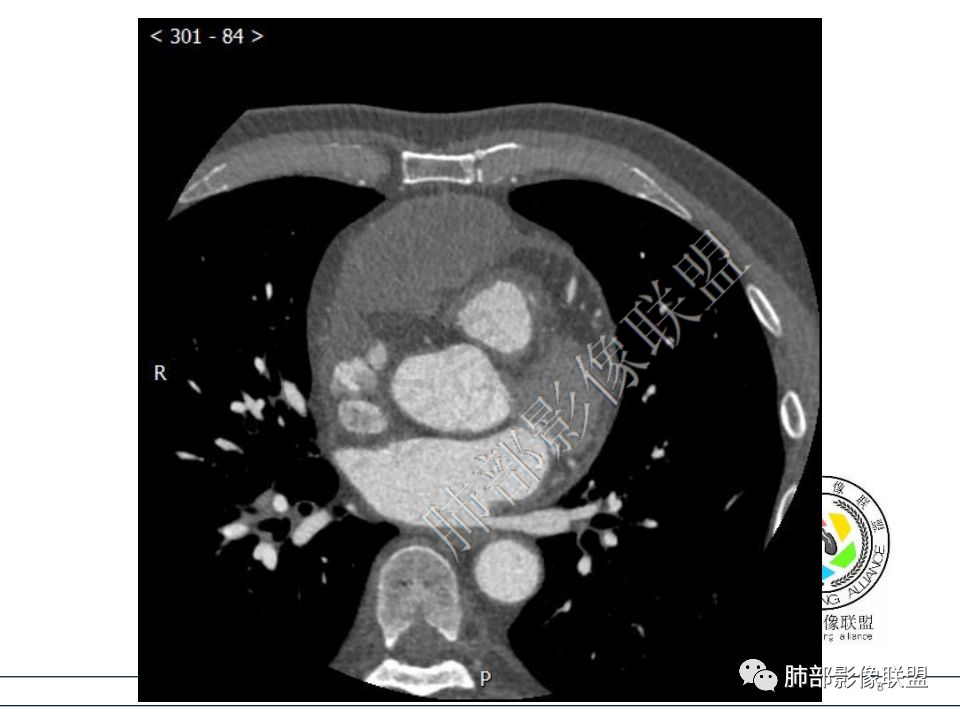

定位心包,形态不规整,结节状突起,与心脏界限模糊,考虑心包间皮瘤。

心包结节状增厚,右房室受压,考虑心包转移瘤? 医学百科网 | YxBaike.Com

病例3 心包肿块,向心包内外生长,可见类似胸膜尾征,右心室受压变形,心包积液病史,恶性间皮瘤,鉴别转移瘤。 医学百科网 | YxBaike.Com

脂肪间隙消失,临近心包增厚,定位心包,定性恶性。 医学百科网 | YxBaike.Com

支持转移,间皮瘤应该多发结节部分融合成片。

右室受压,但是脂肪间隙消失,跟第一例完全不同。

恶性的大家都没问题,不统一的是恶性间皮瘤还是转移瘤。

转移瘤一般侵犯心包局部同时累及心肌,心包积液量一般没有恶性间皮瘤大。 医学百科网 | YxBaike.Com

恶性间皮瘤肿瘤脱落在心包内转移,病变多发,大量心包积液。 医学百科网 | YxBaike.Com

符合恶性间皮瘤,肿瘤侵及右侧心室肌壁。 医学百科网 | YxBaike.Com